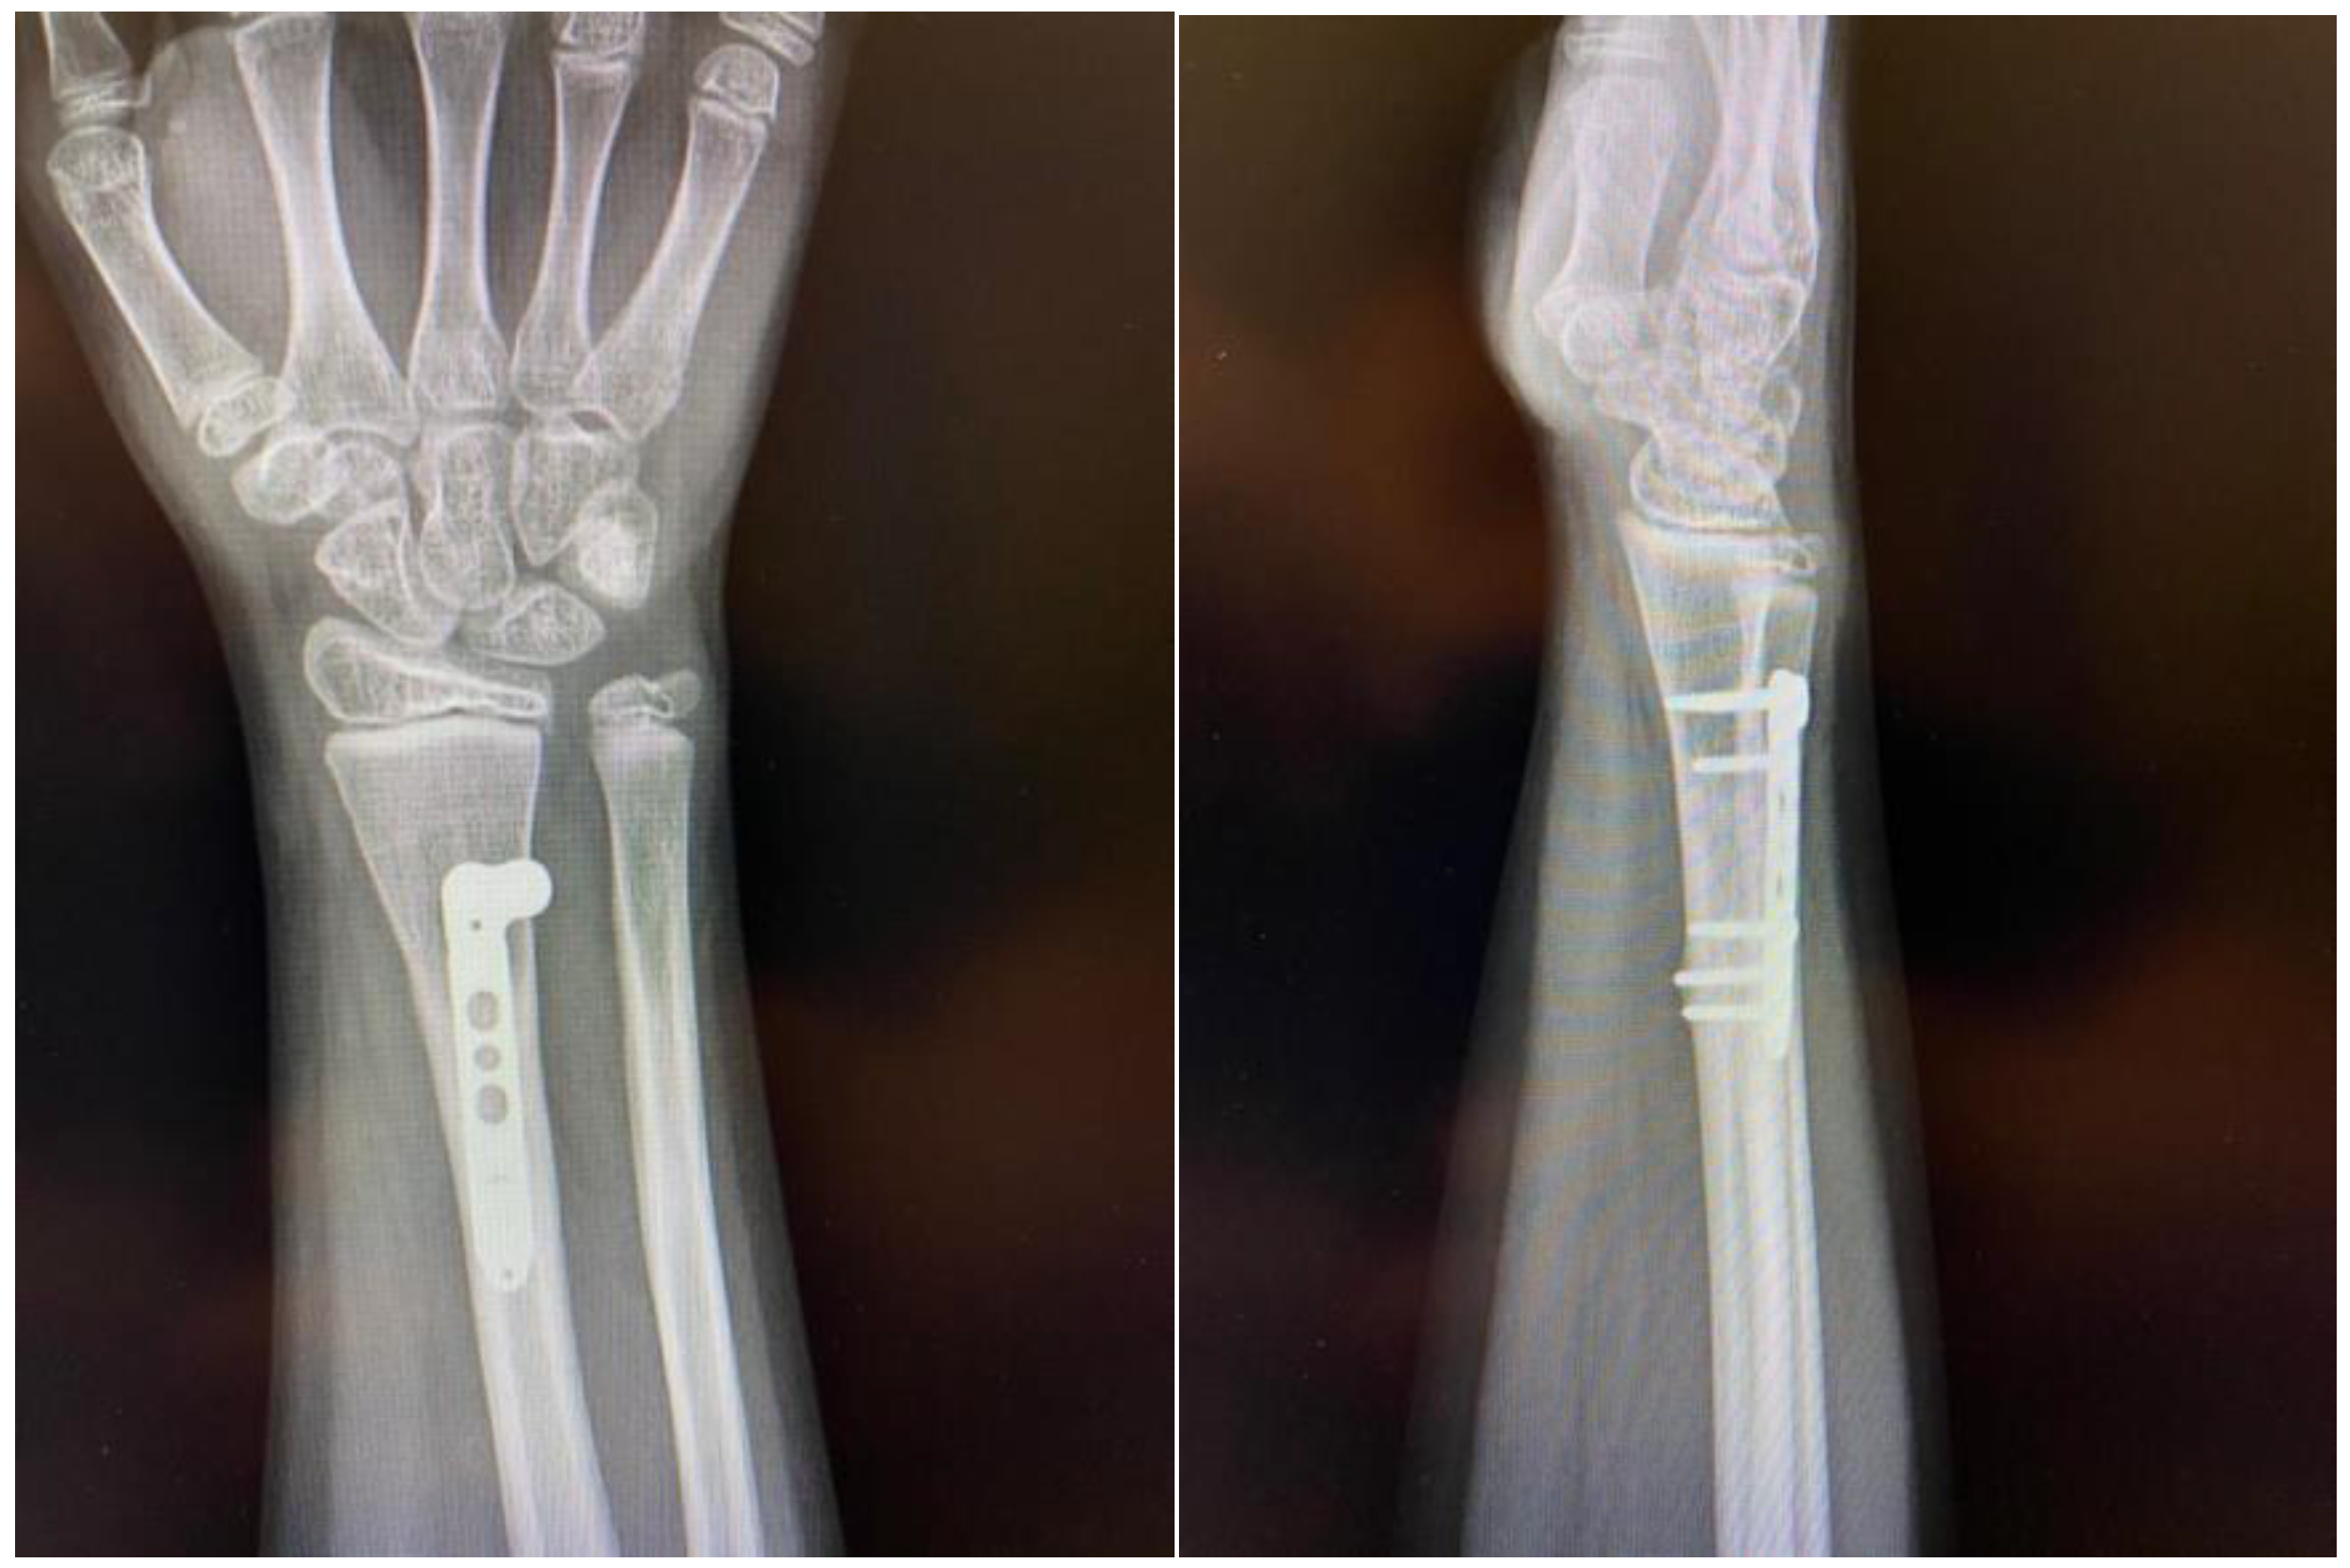

A plain X-ray at initial presentation confirmed a fracture of the distal third of the radius with important displacement and volar angulation >30° (Figure 1A). At presentation, orthopedic reduction was the first gesture but this failed by orthopedic means with a non-successful conservative attempt.

Figure 1. Radiological images obtained at presentation: AP (antero-posterior) (A) and oblique (B) view of the distal forearm, demonstrating important volar displacement of the radial fracture, and greenstick fracture of the distal ulna with dorsal angulation. Also, the fracture presented with a rotational displacement of the distal radial fragment together with the radiocarpal complex.